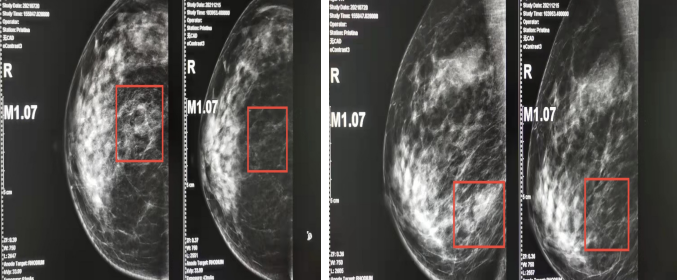

钼靶(2021-12-15):右乳房下象限肿局部腺体稍紊乱,可见条片状稍高密度影,伴多发点状,粗点状钙化灶。双腋窝未示明显肿大淋巴结影。

图6.2021-07-20钼靶图(左)vs2021-12-15钼靶图(右)